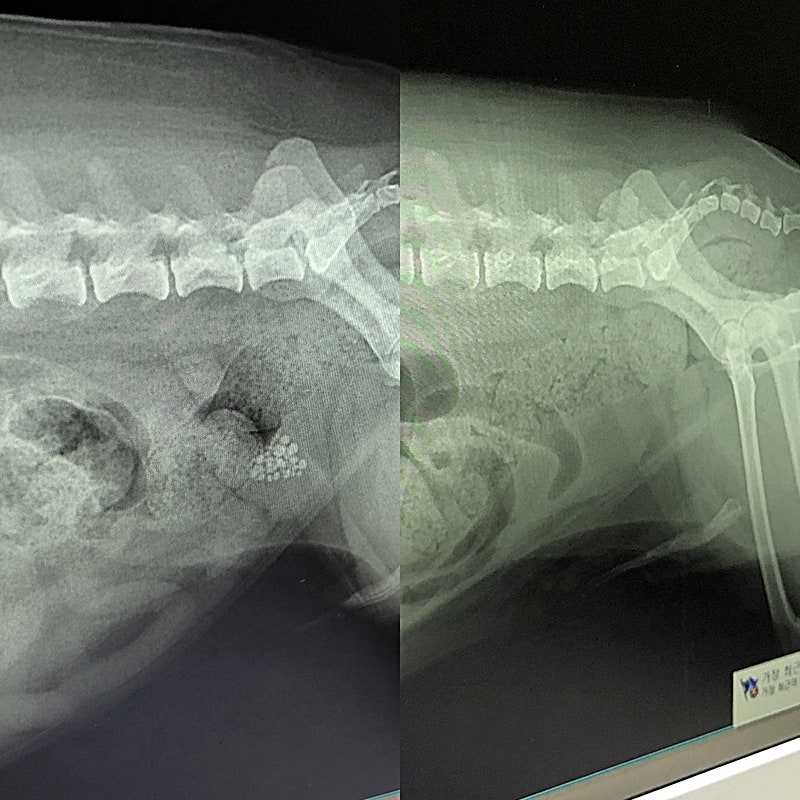

호두는 방광 결석으로 꾸준히 관리해 온 강아지다. 하지만 수술은 불가피했고 결국 수술을 받았다. 예정대로라면 윗집 리모델링이 끝나고 장마가 끝나고 수술을 받으려고 했는데 호두가 밤새 화장실에 왔다갔다 해서 잠을 못자 너무 불쌍해서 수술을 빨리 받는 게 좋다. 생각하고 비가 오지 않는 날 일기예보를 보고 수술 날짜를 정했다. 호두 방광 초음파 방광에 큰 돌멩이가 들어 있다.

오후 1시쯤 병원에서 전화가 와서 수술을 무사히 마치고 오후 4시쯤 데리러 오라고 해서 4시에 데리러 갔다.호두방광속에서 나온 결석…정말 커(울음)선생님 엄지손톱보다 커(울음) 이걸 방광에 넣었다니(울음) 미안해. 눈물 눈물